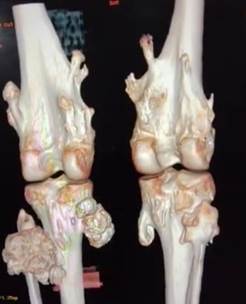

Reconstructed

3D imaging showed multiple sessile and pedunculated exostosis noted in multiple

visualized bones, largest measuring 6.2 x 6.2 x 6.6cm. Pedunculated

metaphyseal exostosis away from joint space in the medial aspect of proximal

tibia with calcification of chondroid matrix, suggesting the possibility of

Osteochondroma with sarcomatous transformation. (Figure 2). There is no

significant family history of any bone lesions.

Figure

2. Reconstructed

3D image of the patient showing multiple pedunculated mass over the tibia and

fibula.